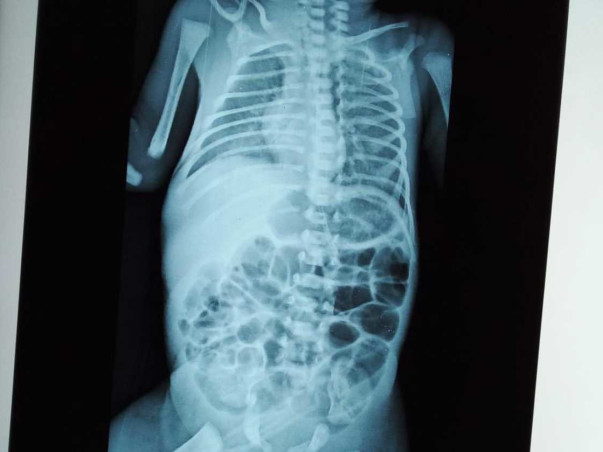

This Is B/o Manasa Chiguru, 7 Days Old, Male Baby, who has Been Under Our Treatment Since The Day Of Birth 03-may-2021. he Has Been Diagnosed With Moderate( Preterm/SGA/vlbw/respiratory Distress-congenital Pneumonia/early On Set Sepsis With Thrombocytopenia And Coagulopathy/hyponatremia/hypoglycemia. Baby Is Been Treated With Broad Spectrum Iv Antibiotics, Positive Pressure Ventilation, Iv Along With Other Supportive Management While Nursing Baby In Thermos Neutral Environment Under The Strict Aseptic Precautions. In The View Of Above Clinical Complications, Baby Requires Another 2-3 Weeks Of Hospital Stay. Which May Amount To Be Expensive Of 6 Lakh INR.